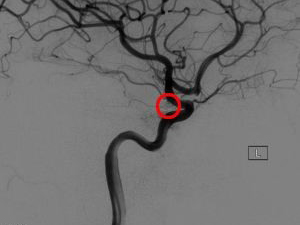

出國看病:腦動脈瘤嚴(yán)重嗎?腦動脈瘤是大腦動脈上的一個薄弱部位,容易膨脹或充血。膨脹的動脈瘤會對神經(jīng)或腦組織造成壓力。它也可能爆裂或破裂,將血液濺到周圍的組織中(稱為出血)。動脈瘤破裂會導(dǎo)致嚴(yán)重的健康問題,如出血性中風(fēng)、腦損傷、昏迷,甚至死亡。腦動脈瘤嚴(yán)重嗎?所以對于未破裂的腦動脈瘤患者來說,并不會嚴(yán)重影響生活,但是腦動脈瘤每年大約1%有破裂風(fēng)險,而破裂出血可能導(dǎo)致腦損傷,甚至有40%的死亡風(fēng)險。

2、微血管夾閉:這個過程包括切斷動脈瘤的血液流動,并需要開顱手術(shù)。醫(yī)生將定位動脈瘤的血管,并在動脈瘤頸部放置一個細(xì)小的金屬針狀夾子,以阻止動脈瘤的血液供應(yīng)。根據(jù)動脈瘤的位置、大小和形狀,夾閉術(shù)已被證明是合適的。一般來說,完全夾閉的動脈瘤不會復(fù)發(fā)。

· 鉑圈栓塞。這是一種比微血管外科夾閉更小的侵入性手術(shù)。醫(yī)生會將一個空心塑料管(導(dǎo)管)插入動脈,通常在腹股溝,并將它穿過身體到腦動脈瘤。使用電線,醫(yī)生將通過導(dǎo)管可拆線圈(微小的螺旋鉑絲),并釋放到動脈瘤。線圈阻塞動脈瘤,減少血液流入動脈瘤。這個手術(shù)可能需要在人的一生中進(jìn)行不止一次,因為用彈簧圈治療的動脈瘤有時會復(fù)發(fā)。

· 導(dǎo)流裝置其他血管內(nèi)治療方案包括在動脈內(nèi)放置類似于心臟阻塞的小支架(柔性網(wǎng)狀管),以減少動脈瘤的血流。醫(yī)生將一個空心塑料管(導(dǎo)管)插入動脈,通常在腹股溝,并將它穿過身體動脈瘤所在的動脈。這個程序用于治療大的動脈瘤和那些不能通過手術(shù)或鉑圈栓塞治療的動脈瘤。